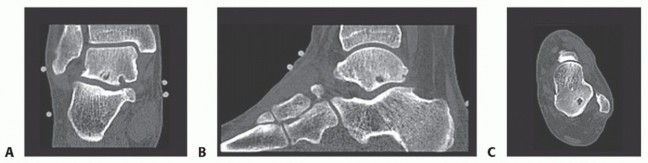

In patients with posterior ankle impingement, the anteroposterior (AP) ankle view typically fails to demonstrate abnormalities (FIG 1A).

On the lateral view, a prominent posterior talar process or os trigonum can sometimes be recognized.

FIG 1 • Imaging of posterior ankle impingement. A. AP ankle view showing no abnormalities. B. Standard lateral view. C. Lateral radiograph with the foot in 25 degrees of external rotation. D. Sagittal CT scan showing os trigonum.

As the posterolaterally located posterior talar process or os trigonum is often superimposed on the medial talar tubercle, detection of an os trigonum on a standard lateral view is often not possible (FIG 1B).

For the same reason, calcifications can sometimes not be detected by this standard lateral view.

We recommend lateral radiographs with the foot in 25 degrees of external rotation in relation to the standard lateral radiographs (FIG 1C).

Computed tomography defines the exact size and location of calcifications, bony fragments, osteochondral lesions, or intraosseous talar cysts (FIG 1D*).

All imaging studies are reviewed to address not only the individual pathology but also the associated bone, cartilage, or ligament injuries, as well as osteophytes, loose bodies, accessory muscles, and calcifications (FIG 2).

FIG 2 • Preoperative planning for débridement and drilling of a subtalar osteochondral cyst lesion in a right ankle. Coronal (A), sagittal (B), and axial (C) CT images showing the subtalar osteochondral defect and secondary cyst lesion.